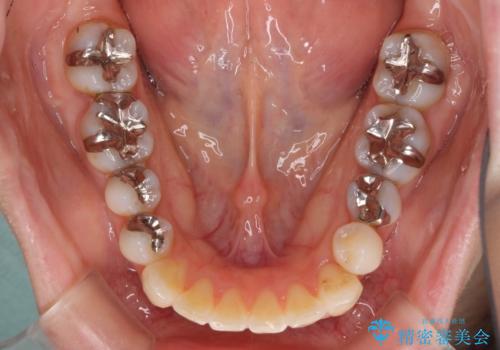

- 前歯のデコボコと矮小歯、更には痛みを感じる奥歯のむし歯を気にして来院された患者様です。

奥歯には根管治療が必要な歯があり、上顎側切歯は左右ともに矮小歯でした。

まずは根管治療を行った上で矯正治療用の仮歯を装着し、矯正治療後半に補綴治療を並行して行うこととしました。